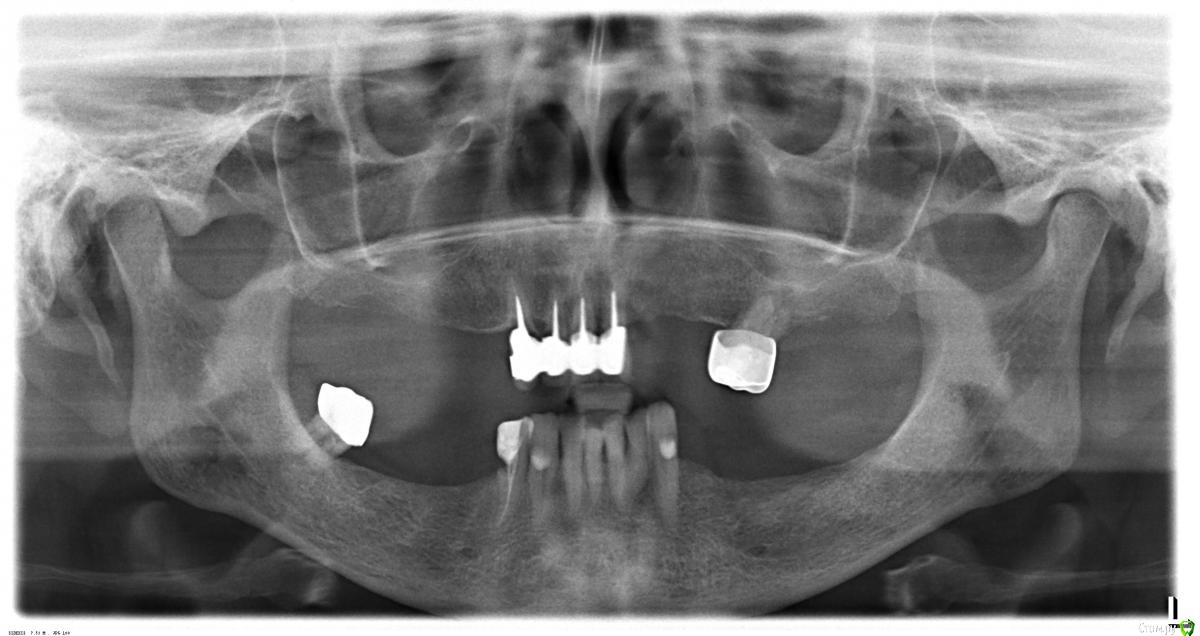

bombazook Опубликовано 8 ноября, 2016 Поделиться Опубликовано 8 ноября, 2016 (изменено) Здравствуйте. Ищем клинику и пытаемся определиться с направлением лечения у матери. Пациентке 67 лет.На верхней челюсти оставшиеся передние зубы болят, нижние передние из-за старого протеза сместились и шатаются.На посещении у имплантолога и ортопеда имплантолог отметил, что снимок плохой, определить по нему ничего невозможно и, соответственно, не дал понять предлагаемый план лечения и вообще удивился желанию пациентки за 60 получить в итоге не шатающиеся стабильные конструкции и имплантаты. Более того, почему-то всё время возникал вопрос "что вы сами хотите получить".Неужели тут всё так безнадёжно, что человек заслужил такое отношение?На полный рот astra-tech бюджета не хватит, да и не в цене проблема. Рассчитываем на средней цены имплантаты, устанавливаемые с соблюдением всех регламентов (шаблоны, рекомендации производителей и пр) и частичное протезирование.Никак не можем понять даже приблизительную нижнюю границу по травматичности, количеству хирургических манипуляций и разумные ожидания по цене и, самое главное, не можем найти клинику для подобного полного и разумного курса лечения.Очень хочется узнать экспертное мнение и получить совет по порядку действий. Спасибо. Изменено 8 ноября, 2016 пользователем bombazook Ссылка на комментарий

Nazim_NV86 Опубликовано 24 ноября, 2016 Поделиться Опубликовано 24 ноября, 2016 Ничего так для 67 лет. Некоторые в 40 такие панорамки приносят. Не забудьте подробно заполнить анкету. Ссылка на комментарий